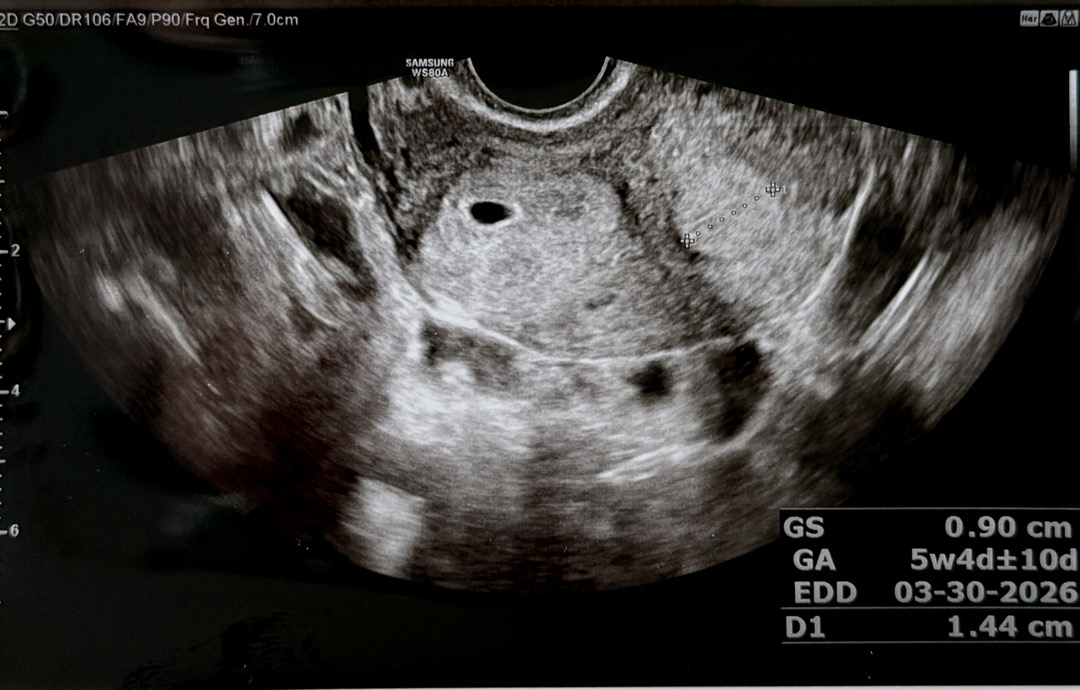

마지막 생리 시작일이 6.27이고 피검사는 7.25 오전에 했는데 수치가 131나왔거든요. 수치가 낮아서 오늘 아기집이 안 보일수도 있겠다고 하셨는데ㅠ 너무너무 선명하게 잘 보고 왔어요🥹 0.9cm...넘 작죠ㅋㅋ 오늘을 5주 0일로 보면 된다구 하시네용..! 게다거 저는 쌍각자궁이라... 혹시라두 자궁각에 착상되었을까봐 노심초사했는데 다행히 그러진 않아보인다구 하셔서 한시름 놨어요ㅠ 아직 난황은 안 보이구 2주뒤에 오라고 얘기해주셨네요. 그때 산모수첩이랑 마미톡 바코드 받을 수 있나봐요. 출산 예정일은 4.5 받았구 임신확인증 발급받아서 부랴부랴 보건소 가서 뱃지도 받고 선물세트도 받아왔습니당ㅎㅎ 다음주부터는 바로 단축근무 할 수 있게 품의 올리려구요!